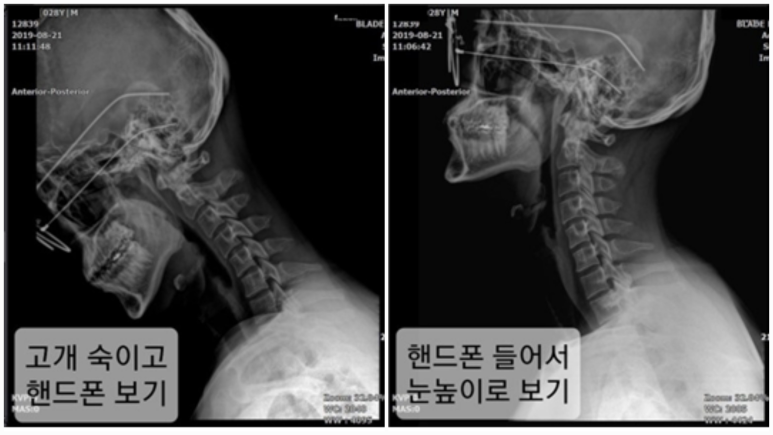

핸드폰을 보는 자세 하나만 바꿔도 목의 곡선이 달라지고, 자세가 달라지면 통증 역시 확연히 달라집니다. 즉, 우리의 몸은 잘못된 습관을 고치고 새로운 움직임 패턴을 만들었을 때 비로소 회복할 수 있는 것이죠.